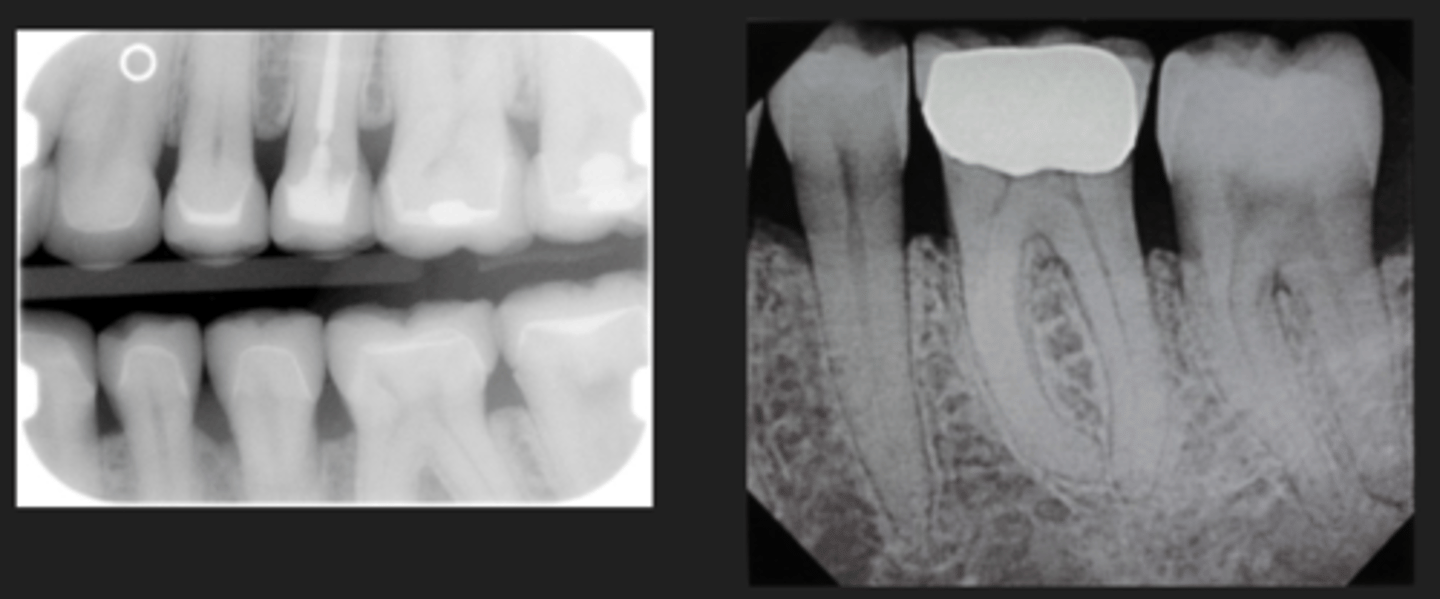

Porcelain restorations

- Varying shades of radiopacity

- > Halo

- Many have a metal substructure

- Some crowns can be all porcelain

Porcelain crowns

- Porcelain-Fused-to-metal (PFM)

Restorative material - Fixed partial dentures/bridge

- Pontic = Missing tooth

- Abutment = Crowned supporting teeth